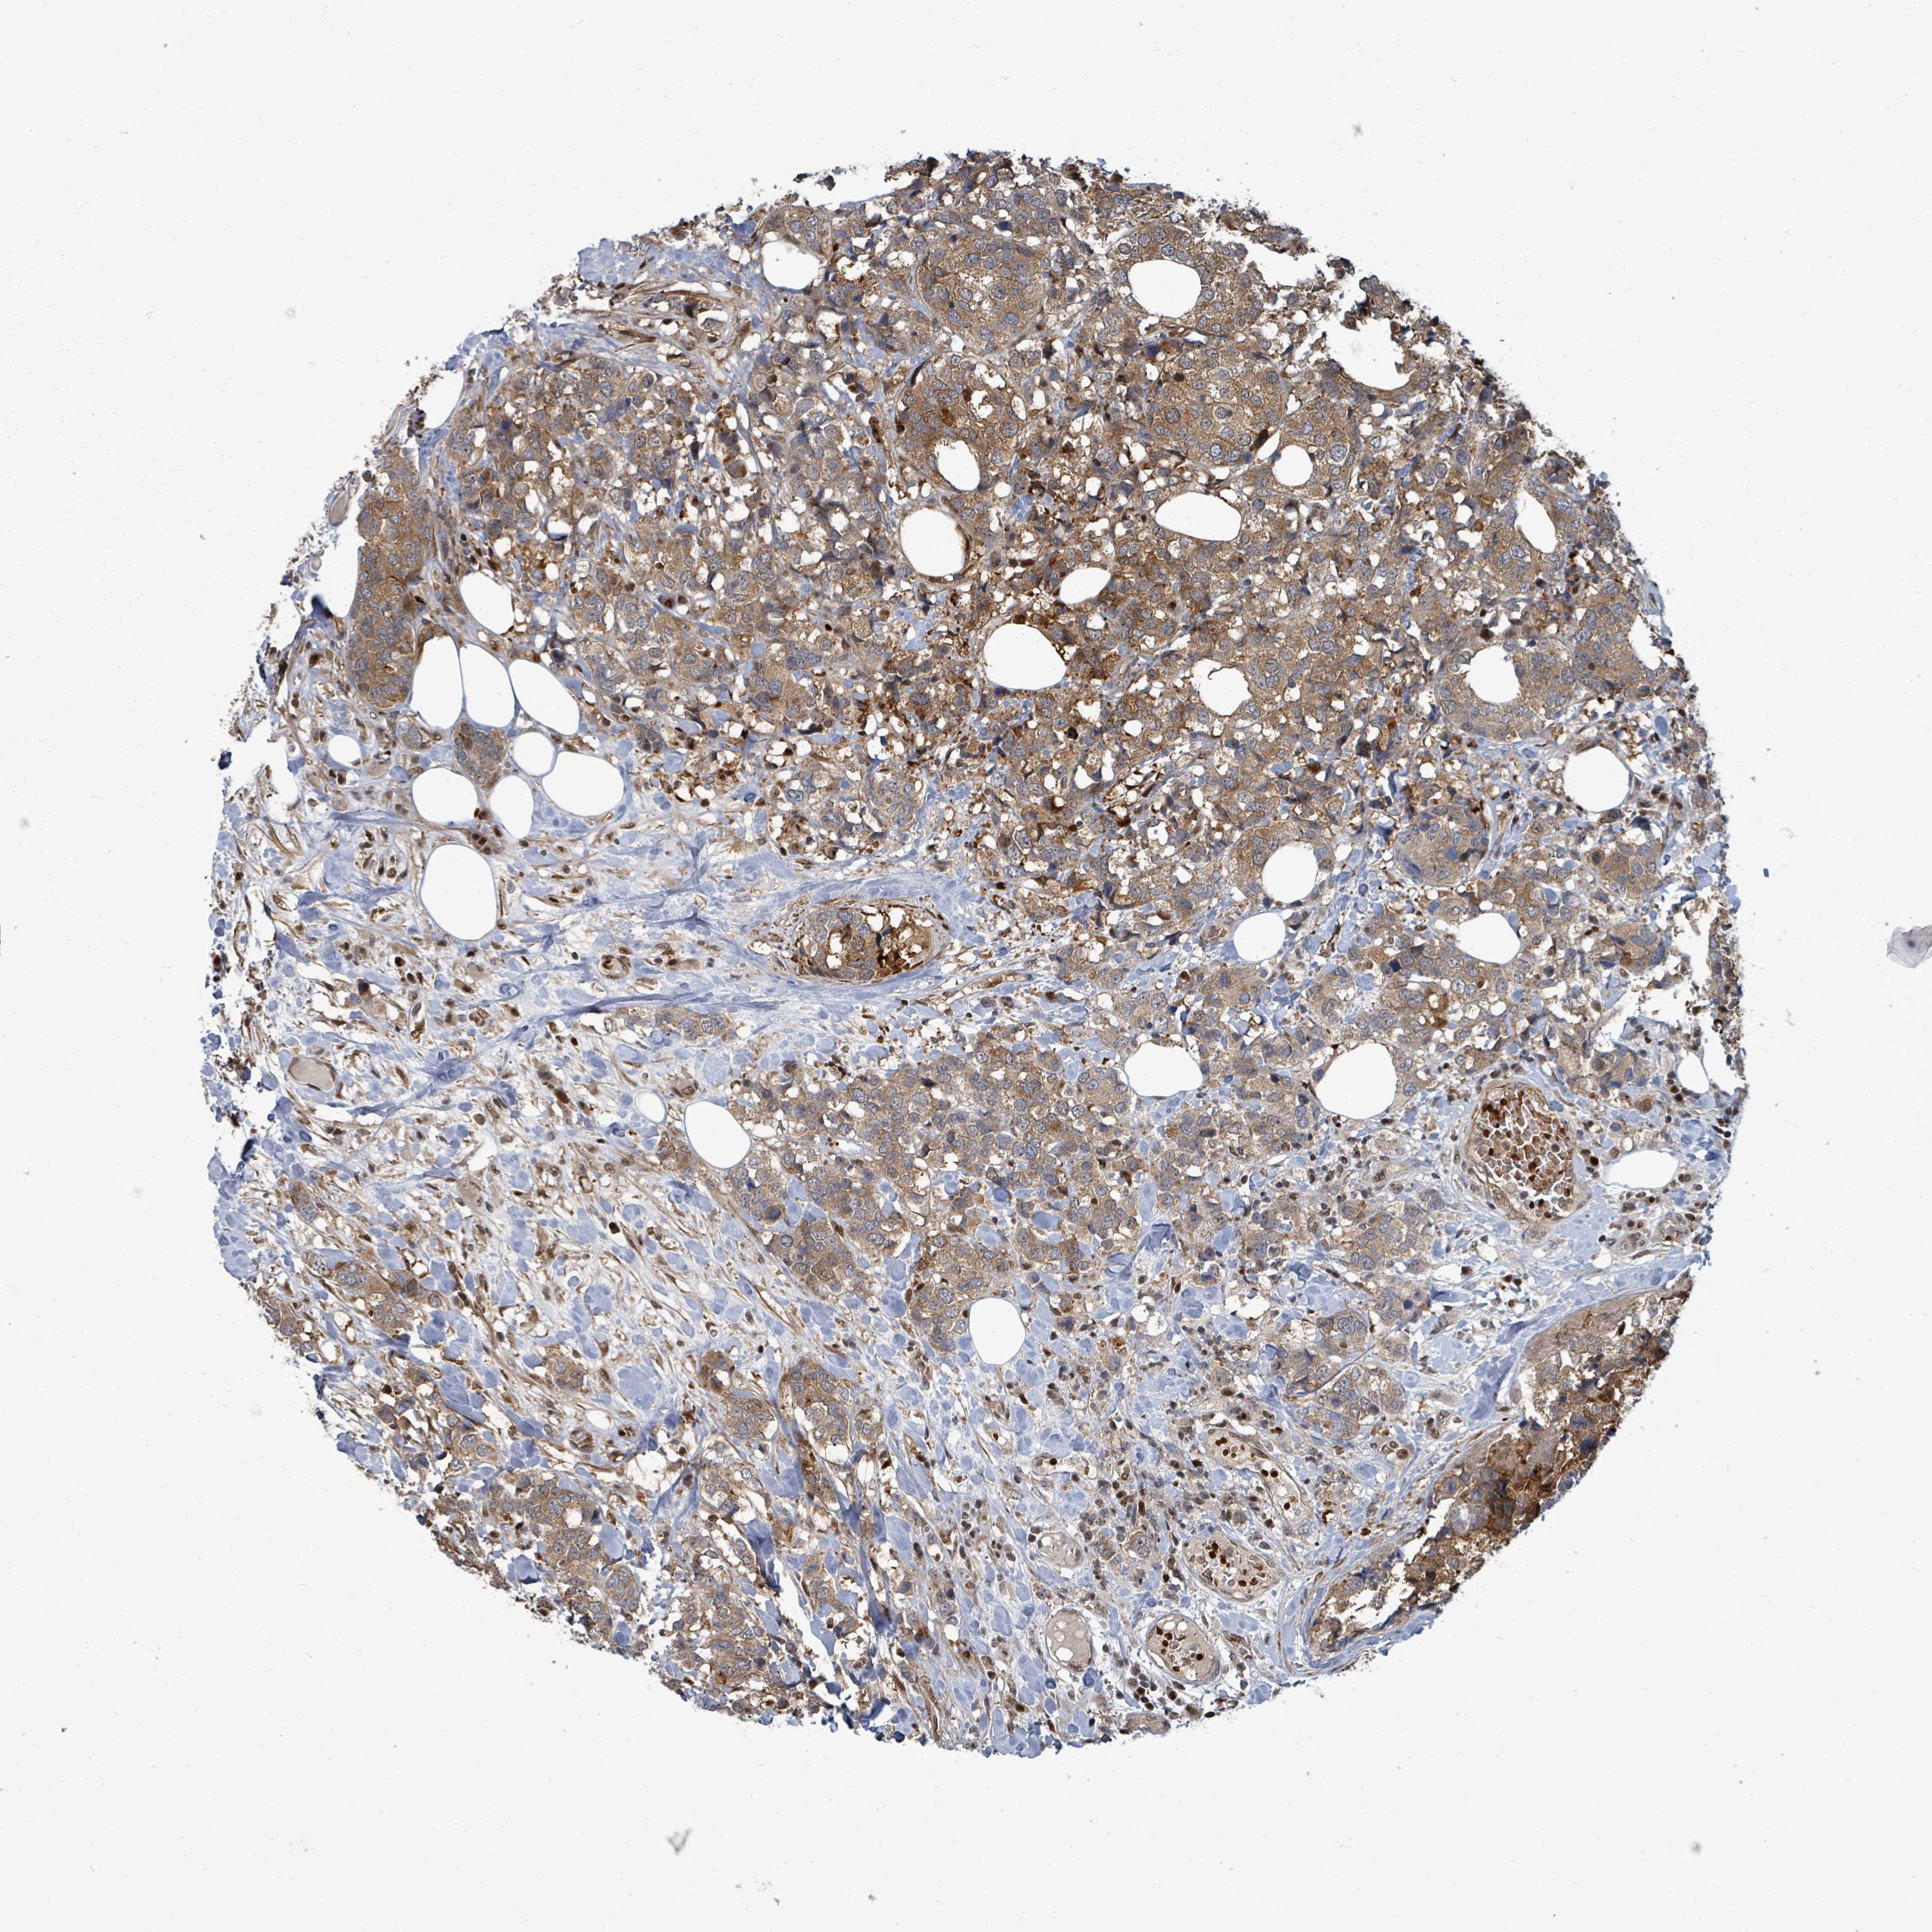

CANCER BREAST CANCER Show tissue menu

BRCA TCGA BRCA VALIDATION PROTEIN EXPRESSION